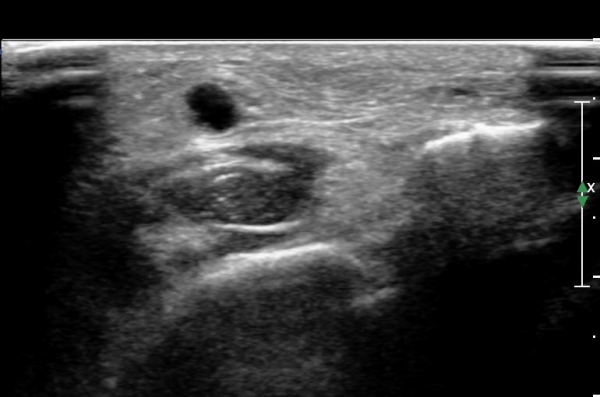

¾Æ·§´Ù¸® ¿ÜÃø Ⱦ´Ü¸é°Ë»ç¿¡¼ Àåºñ°ñ±Ù°ú ¹ß°¡¶ô½ÅÀü±Ù »çÀÌ¿¡¼ õºñ°ñ½Å°æÀÌ Á¤»óÀûÀ¸·Î °üÂûµÈ´Ù(»çÁø 1, , 2, 3, 4, 5).

¾ÕÂÊ ¸»´Ü °æ°ñºñ°ñ°üÀý ¾à 5cm ±ÙÀ§ºÎ Ⱦ´Ü몀°Ë»ç ½Ã õºñ°ñ½Å°æ Àü¸é¿¡ Àú¿¡ÄÚ ³¶Á¾¿¡ ÀÇÇÑ ½Å°æ ¾Ð¹ÚÀÌ °üÂûµÈ´Ù(ÀÌ °üÂûµÈ´Ù(»çÁø 6, 7).